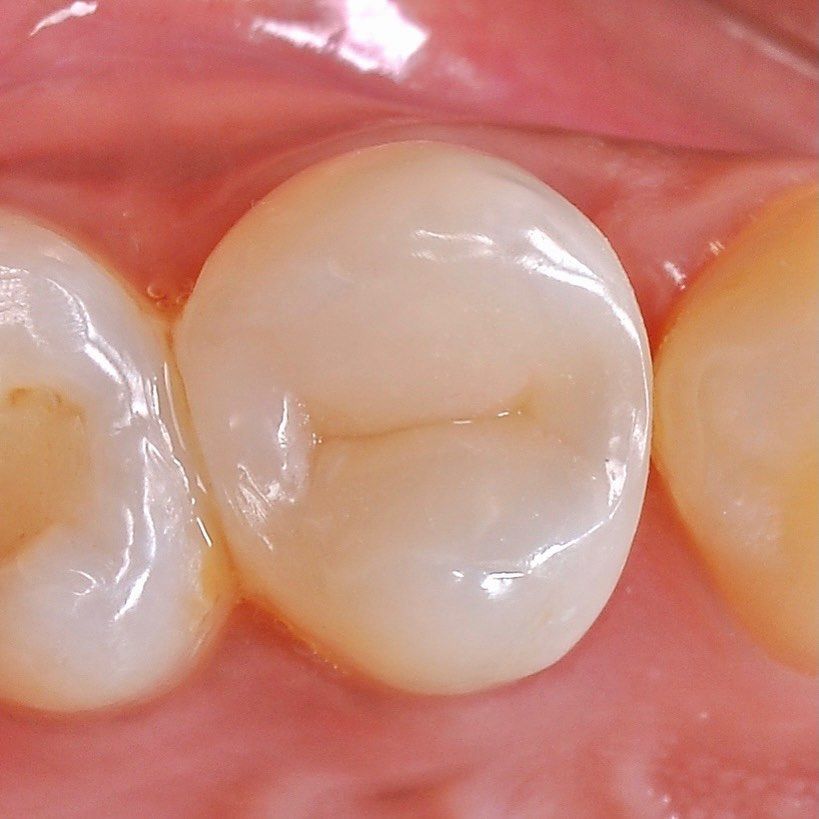

we install a crown on the cured tooth

We prosthetics a tooth, we protect it from the external environment